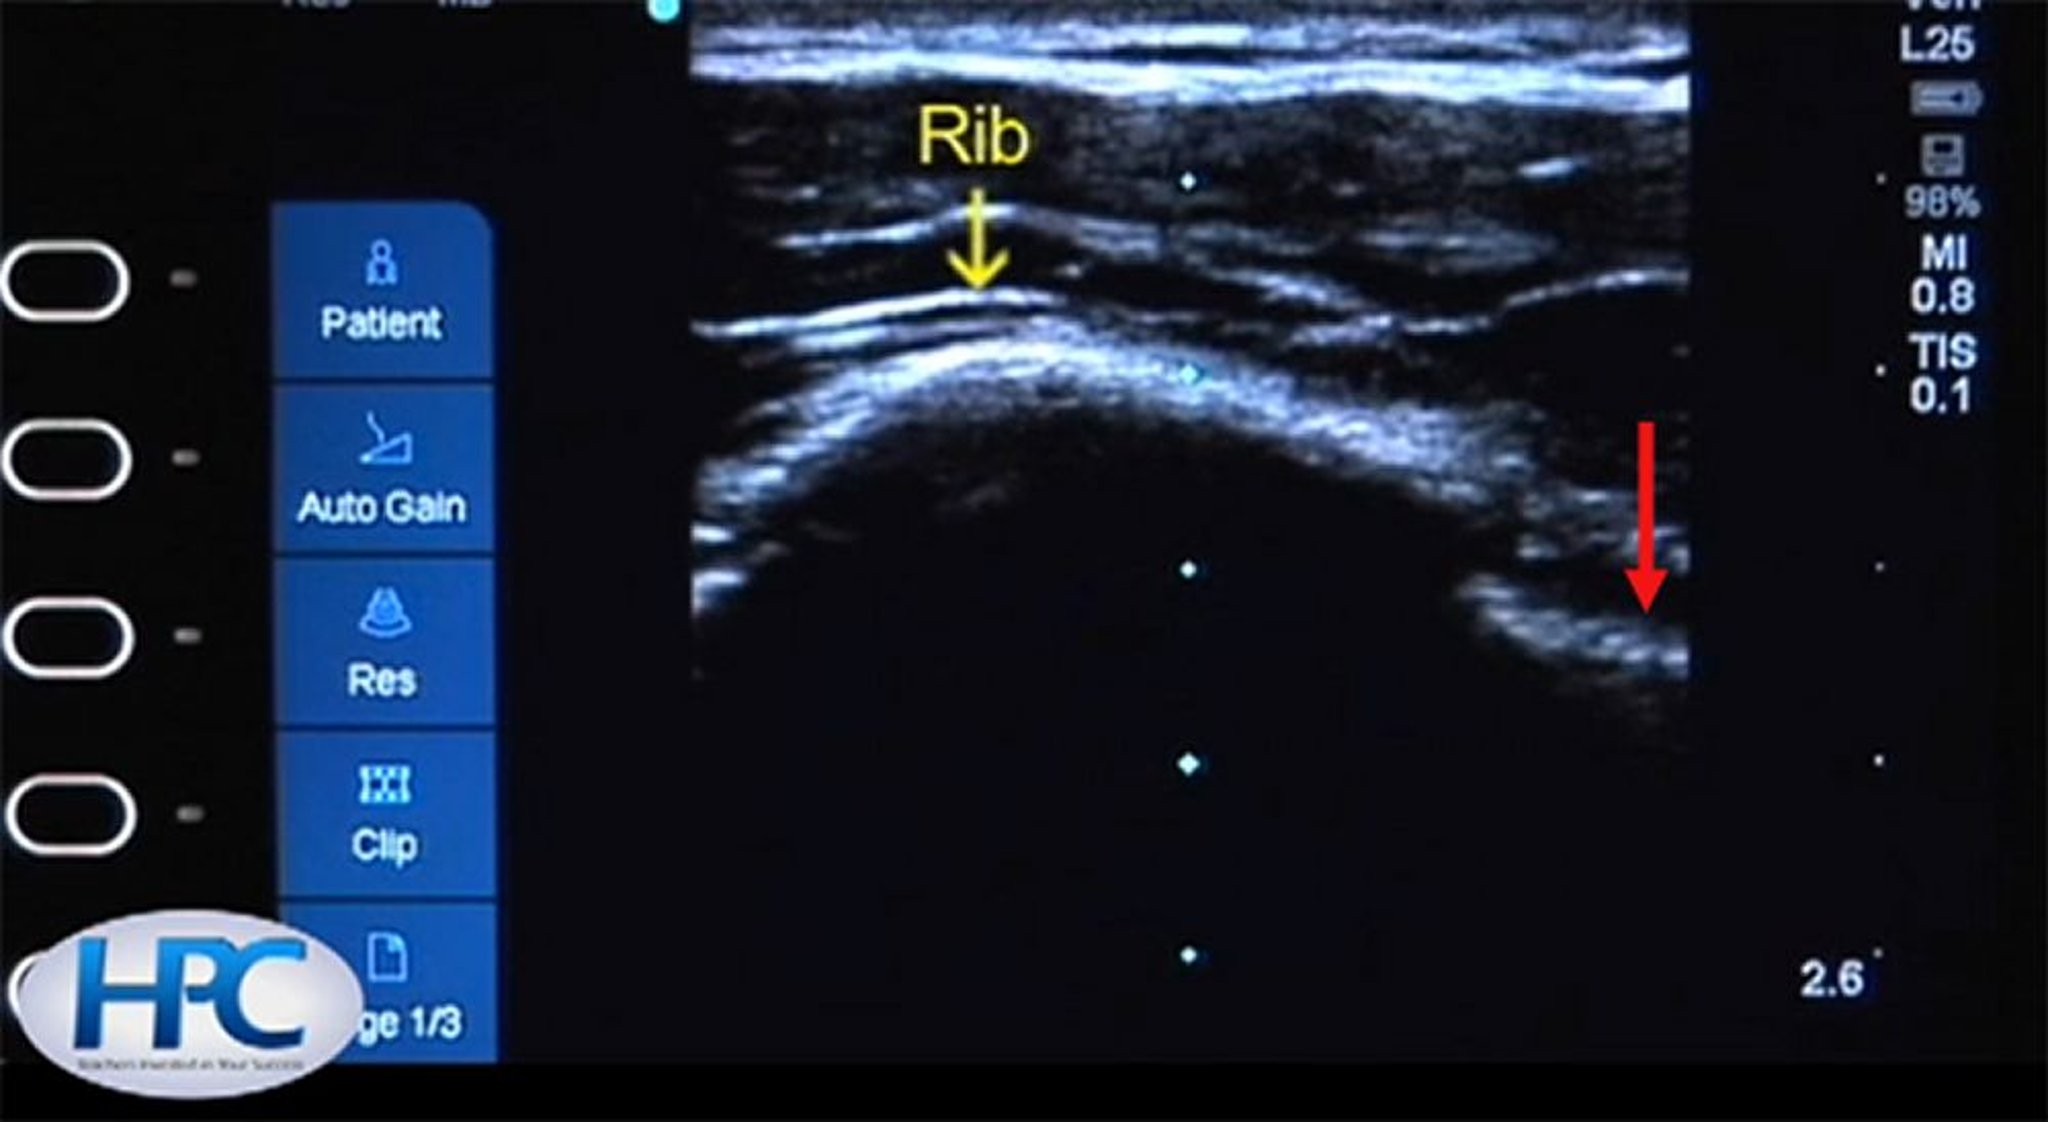

Зображення ребер та лінії плеври при ультразвуковому дослідженні

Ребро (жовта стрілка) виглядає як гіперехогенна (біла) структура із затіненням нижче ребра. Плевральну лінію (червона стрілка) видно у міжреберному просторі.